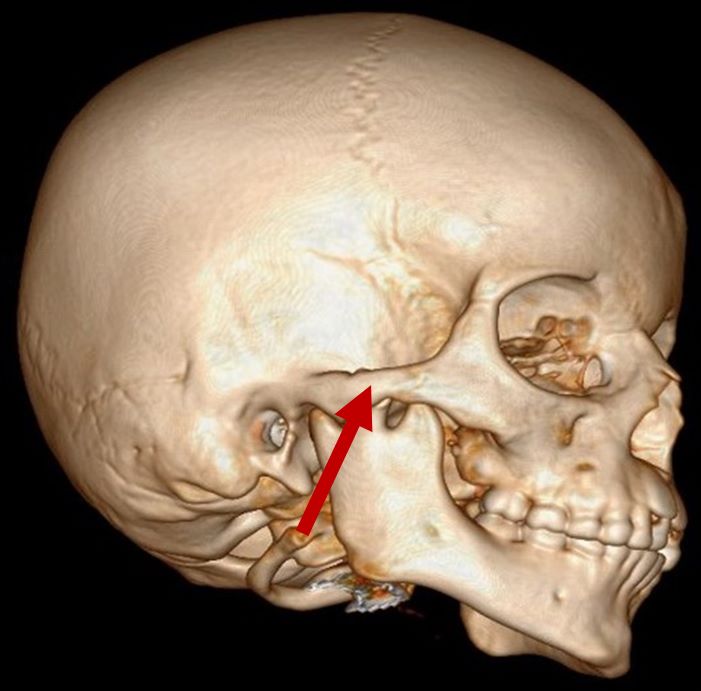

Zygomatic hypoplasia

3D CT scan showing missing zygomatic arch

Radiographical features source 4